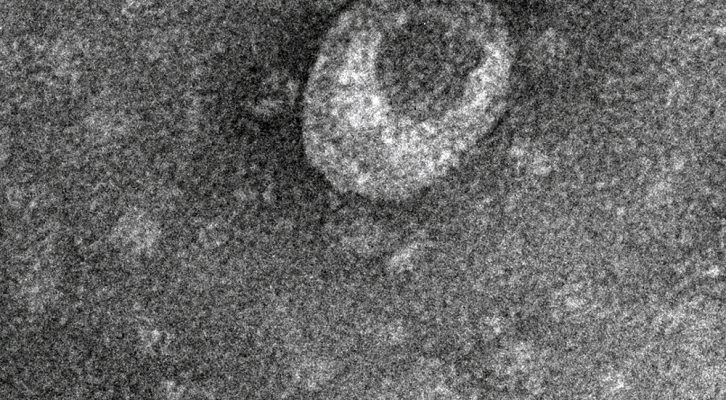

A covid-19 foi a terceira causa de morte nos Estados Unidos, atrás das doenças cardiovasculares e do cancro, segundo...